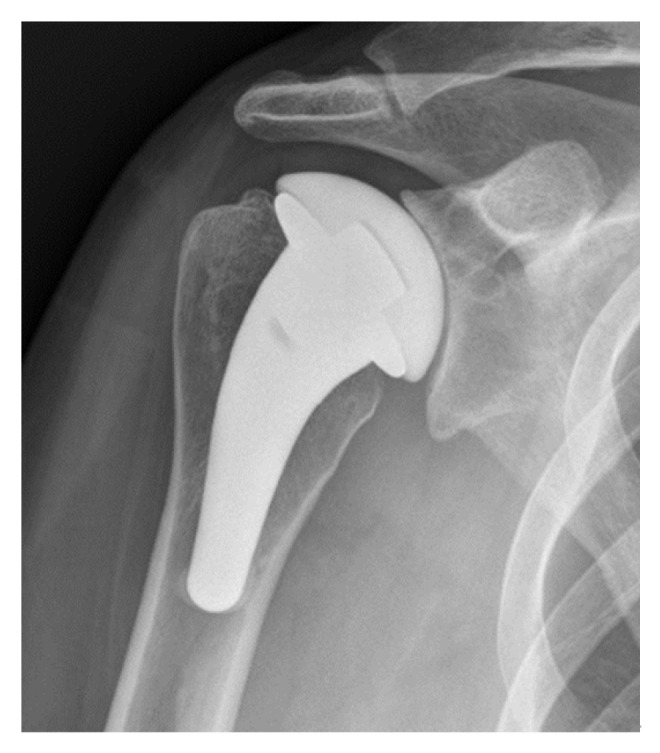

While shoulder hemiarthroplasty is still used to treat young patients with shoulder pathology, the use of this procedure has substantially declined in recent years due to its significant complication profile. Glenoid wear with arthrosis is one of the major postoperative complications following shoulder hemiarthroplasty, and efforts to prevent this complication led many scientists to explore alternative weight-bearing surfaces on arthroplasty implants to decrease joint wear and improve patient outcomes. Pyrolytic carbon, or pyrocarbon, is a material that has better biocompatibility, survivorship, strength, and wear resistance compared to the materials used in traditional shoulder hemiarthroplasty. Pyrocarbon implants have been used in orthopedics for over 50 years; recently, their utility in shoulder hemiarthroplasty has garnered much interest. The purpose behind the use of pyrocarbon in shoulder hemiarthroplasty is to decrease the risk of progressive glenoid wear, especially in young active patients in whom joint preservation is important. Promising survivorship and outcomes have been demonstrated by recent studies, including limited glenoid wear following pyrocarbon hemiarthroplasty. Nevertheless, these clinical studies have been limited to relatively small case series with limited long-term follow-up. Accordingly, additional research and comparative studies need to be conducted in order to properly assess the therapeutic efficacy and value of pyrocarbon hemiarthroplasty.